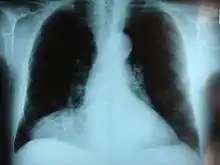

| Morgagni hernia seen on a chest radiograph. | |

Morgagni hernia

This rare anterior defect of the diaphragm is variably referred to as a Morgagni, retrosternal, or parasternal hernia. Accounting for approximately 2% of all CDH cases, it is characterized by herniation through the foramina of Morgagni which are located immediately adjacent and posterior to the xiphoid process of the sternum.[4]